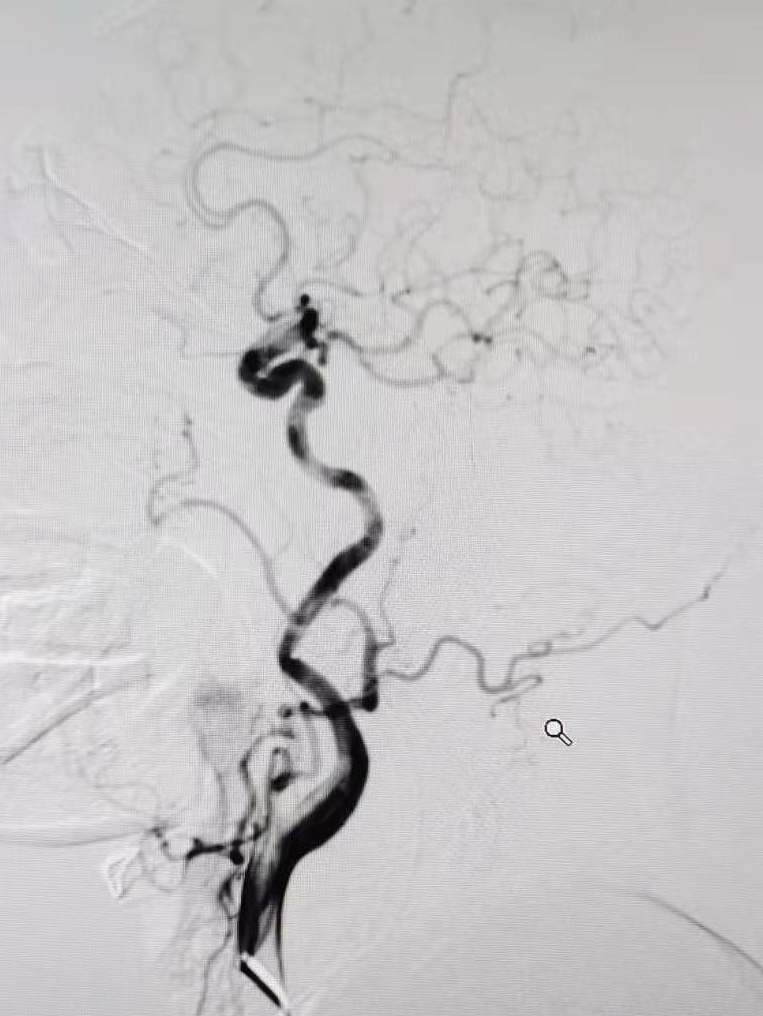

全脑血管造影提示右侧椎动脉颅内段闭塞,左侧椎动脉颅外段走形迂曲,基底动脉近端闭塞。

5F 115cm远端通路导管超选至左侧椎动脉V2段,选取术中工作角度造影。

通过微导丝微导管技术,0.014in微导丝通过闭塞血管,将Rebar 18微导管管头置入基底动脉中段,微导管内造影确保在血管真腔内。